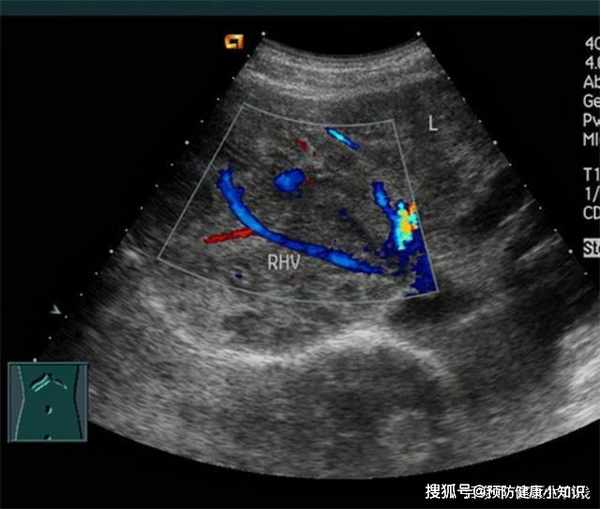

患者體溫37.8℃、血壓125/90、身高183cm、體重75kg。患者腹部壓痛、反跳痛明顯,腹部彩超檢查結果顯示肝臟存在多處病變,均為惡性,腹腔淋巴結腫大;癌胚抗原5.3 ng/ml;乙肝表面呈陽性。最終診斷為原發性肝癌晚期。